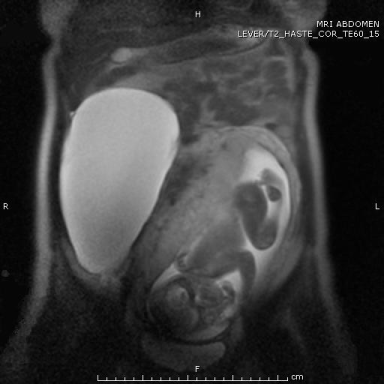

In 2006, a 26-year old female, pregnant with her first child, presented for a regular check-up. Gestational age of the child was nineteen weeks. During routine US, a space occupying lesion was discovered next to the uterus with a size of 15 x 12 x 6 cm, transonic, with bright echo density, initially diagnosed as a pathologic cystic lesion of the right ovary. However, as there were no other findings supporting a malignant diagnosis, tumor markers CEA, alfa-fetoprotein and CA125 were within normal range, and the intra-uterine pregnancy was intact, watchful waiting was indicated. Over twenty weeks later, the patient delivered a healthy female baby after a spontaneous, uncomplicated childbirth. Several weeks following delivery the patient was examined and was found to have normal internal genitalia; therefore, in February 2007 abdominal MRI with gadolinium was performed, showing a sharply demarcated additional structure, with a hypo-intense dimension on T1-weighed haste and highly hyper-intense dimension on T2 weighed haste, with no contrast uptake of gadolinium. It was defined a cystic lesion, most compatible with a benign mesenteric cyst (Figure 1). Therefore, the patient was referred to the surgeon in order to arrange total cyst resection by laparotomy. Due to personal circumstances, including a second pregnancy, the operation was postponed for many years. In 2013, the patient returned to department of surgery with complaints of symptomatic abdominal distention, specifically on the left side of the abdomen. These complaints have been present for a few months and are slowly progressive. She has no complaints of pollakiuria or urgency. By this time, she reached the age of 32 and had no accompanying symptoms such as weight loss or malaise. A CT scan was performed, showing progressive growth of the cystic mass, with compression of the bladder (Figure 2). Apart from the progressive growth, there were no signs of malignant transformation, invasion of other organs or lymfadenopathy.

Figure 2: CT scan after 66 months demonstrates the progressively grown cyst, with a cranio caudal diameter of 27 cm with bladder compression. There was no relation between cyst, uterus and ovaries, during scan no lymphadenopathy could be demonstrated consistent with a large mesenteric cyst.